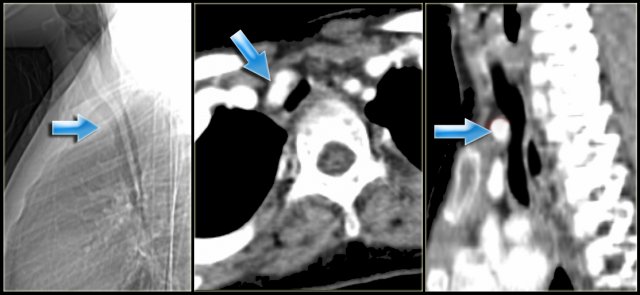

Innominate artery compression syndrome with compression of the trachea Innominate artery compression syndrome with compression of the trachea

Innominate artery compression syndrome

On the left a sagittal scanogram, axial image and sagittal reconstruction of a 5 year old girl with noisy breathing and occasional episodes of cyanosis.

The findings are:

1. anterior compression of the trachea

2. brachiocephalic (innominate) artery is located more to the left and compresses the trachea

The diagnosis is the innominate artery compression syndrome.

In infants the innominate artery arises more to the left than in adults, so it's got to go in front of the trachea. It may compress the trachea, leading to stridor, cough and dyspnea. This compression decreases with age and these patients will outgrow it.

The compression in the innominate artery compression syndrome is located on the right anterior side and at the level of the thoracic inlet.

This is much higher than in the double arch or Right Aortic Arch with Aberrant left subclavian